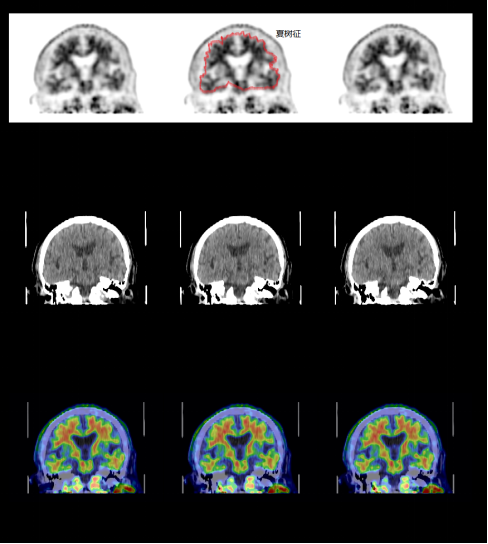

阿尔茨海默病(AD),也就是常说的老年痴呆,是最常见的痴呆类型。我国是痴呆人数最多的国家,65 岁以上人群中,痴呆发生率超 5%,其中 AD 占比超 50%,患者人数超 700 万。

查看详情